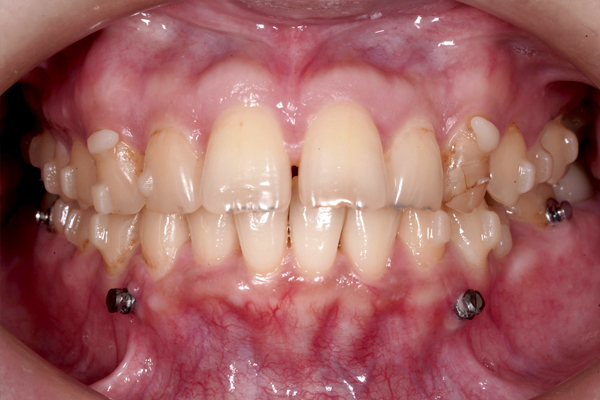

正面の比較

治療開始から9か月が経過し、前歯の重なりは徐々に改善し、上の前歯も少しずつ後方へ移動しています。見た目にも変化が現れはじめており、治療は順調に進んでいます。

本治療では、インビザラインを用いた非抜歯矯正を行っています。治療の進行にあわせて、インプラントアンカーを使用し、歯を後方へ移動させる計画です。治療期間はおよそ1年6か月を予定しており、現在は開始から9か月が経過した段階です。

現在、治療開始から9ヶ月が経ちました。

マウスピース矯正は患者さまの使用頻度によって治療の成績が大きく変わってしまいます。マウスピース以外にゴムを使用しています。患者さまは真面目に矯正治療に取り組んでいただいています。このまま最後まで頑張っていきましょう。